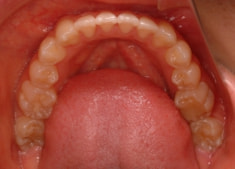

治療後(2年3ヶ月後)